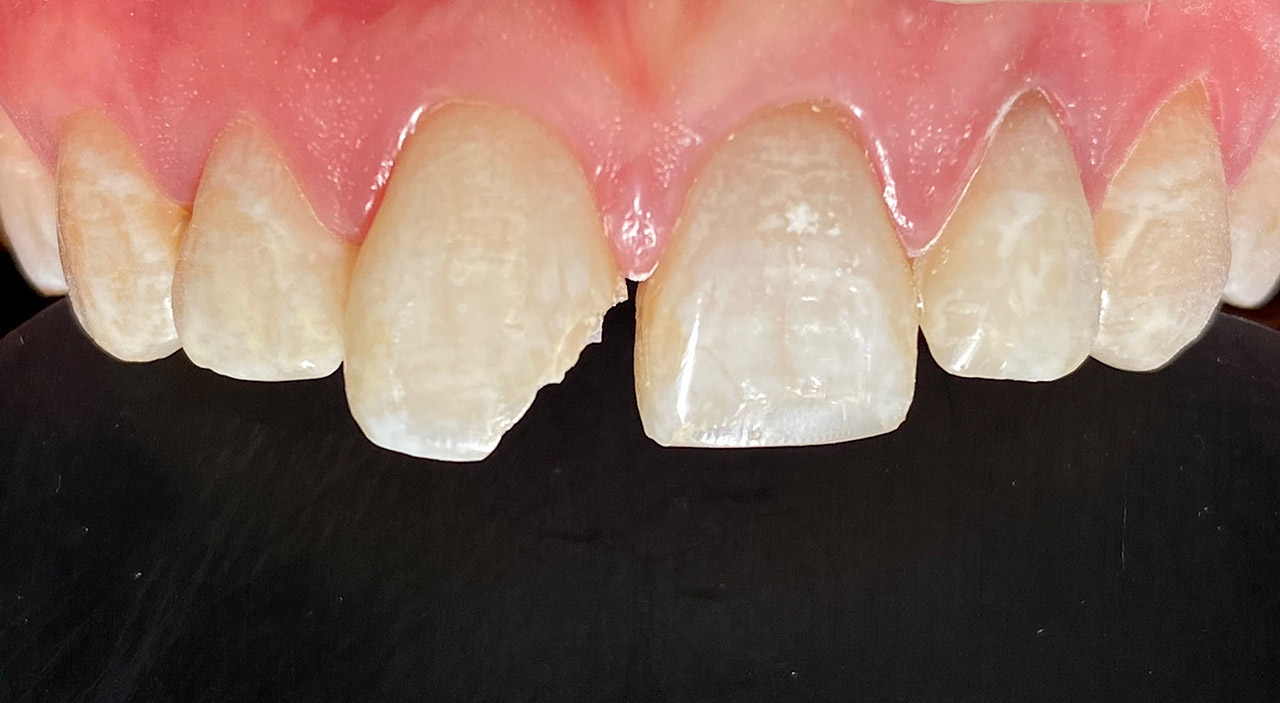

Traumatologie und Endodontie:

Nach Unfall/Sturz mittlerer Schneidezahn auf Gingivaniveau abgebrochen, Pulpa weit eröffnet, beide Nachbarzähne ebenfalls frakturiert.

Erstversorgung: Pulpektomie der Kronenpulpa, MTA, provisorischer Verschluß mit rosa Glasionomerfüllung.

Wiederaufbau der Nachbarzähne mit mitgebrachten (plus 1 Stein) Zahnstücken mit Kunststoff ergänzt und adhäsiv verklebt.

2. Schritt nach Aushärtung von MTA: Entfernung der Kronenpulpa im Bruchstück zur Vermeidung von Verfärbung, Füllung mit Kunststoff.

Adhäsives zementieren des abgebrochenen Zahnstücks.